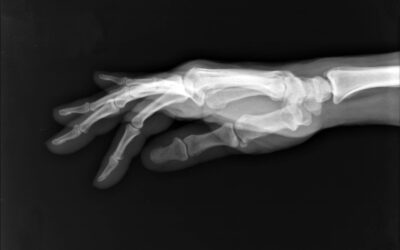

Basilar Thumb Arthritis – CMCJ OA

What is basilar thumb arthritis? Basilar thumb arthritis is common with aging and occurs when cartilage wears away from the ends of the bones that form the joint at the base of your thumb — also...